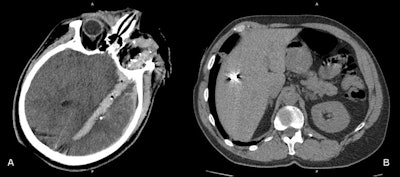

War injuries like these four cases are encountered on a daily basis at Zaporizhia Regional Hospital. (A) Penetrating gunshot wound. The wound channel passes through the left orbit and the left hemisphere of the brain, containing blood, air bubbles. and metal debris. (B) Shrapnel wound of the liver. (C) Gunshot wound of left hemithorax. The wound channel passes through the left lung with contusion of perifocal parenchyma, left pneumothorax, mediastinal and left subcutaneous and intramuscular emphysema. (D) Gunshot wound of left orbit and left maxillary sinus with multiple metal pellets and hemosinus. Images courtesy of Dr. Andrii Makarenkov.

War injuries like these four cases are encountered on a daily basis at Zaporizhia Regional Hospital. (A) Penetrating gunshot wound. The wound channel passes through the left orbit and the left hemisphere of the brain, containing blood, air bubbles. and metal debris. (B) Shrapnel wound of the liver. (C) Gunshot wound of left hemithorax. The wound channel passes through the left lung with contusion of perifocal parenchyma, left pneumothorax, mediastinal and left subcutaneous and intramuscular emphysema. (D) Gunshot wound of left orbit and left maxillary sinus with multiple metal pellets and hemosinus. Images courtesy of Dr. Andrii Makarenkov.The department's equipment includes a Toshiba Activion16 CT scanner and a stationary angiographic C-arm Toshiba INFX-8000V machine. Medical staff usually continue working during air raids and rocket attack sirens. Sometimes the electricity is cut during CT scans. Contrast media and other consumables are in sufficient quantity for the moment, he noted.